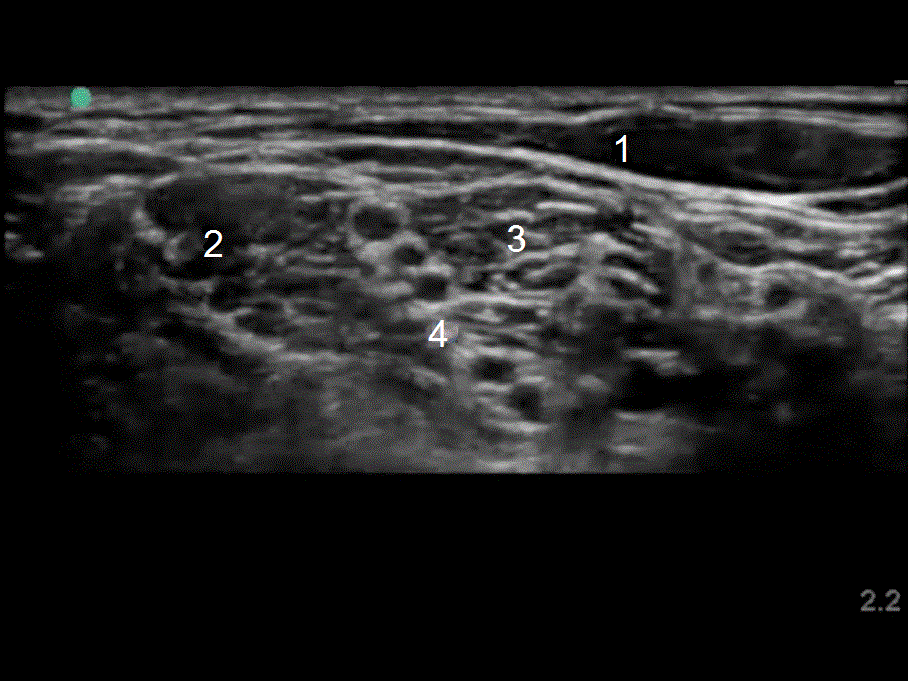

Interscalene Nerve Block - Anatomy with Ultrasound Image

1. Sternocleidomastoid Muscle

2. Middle Scalene Muscle

3. Anterior Scalene Muscle

4. Brachial Plexus